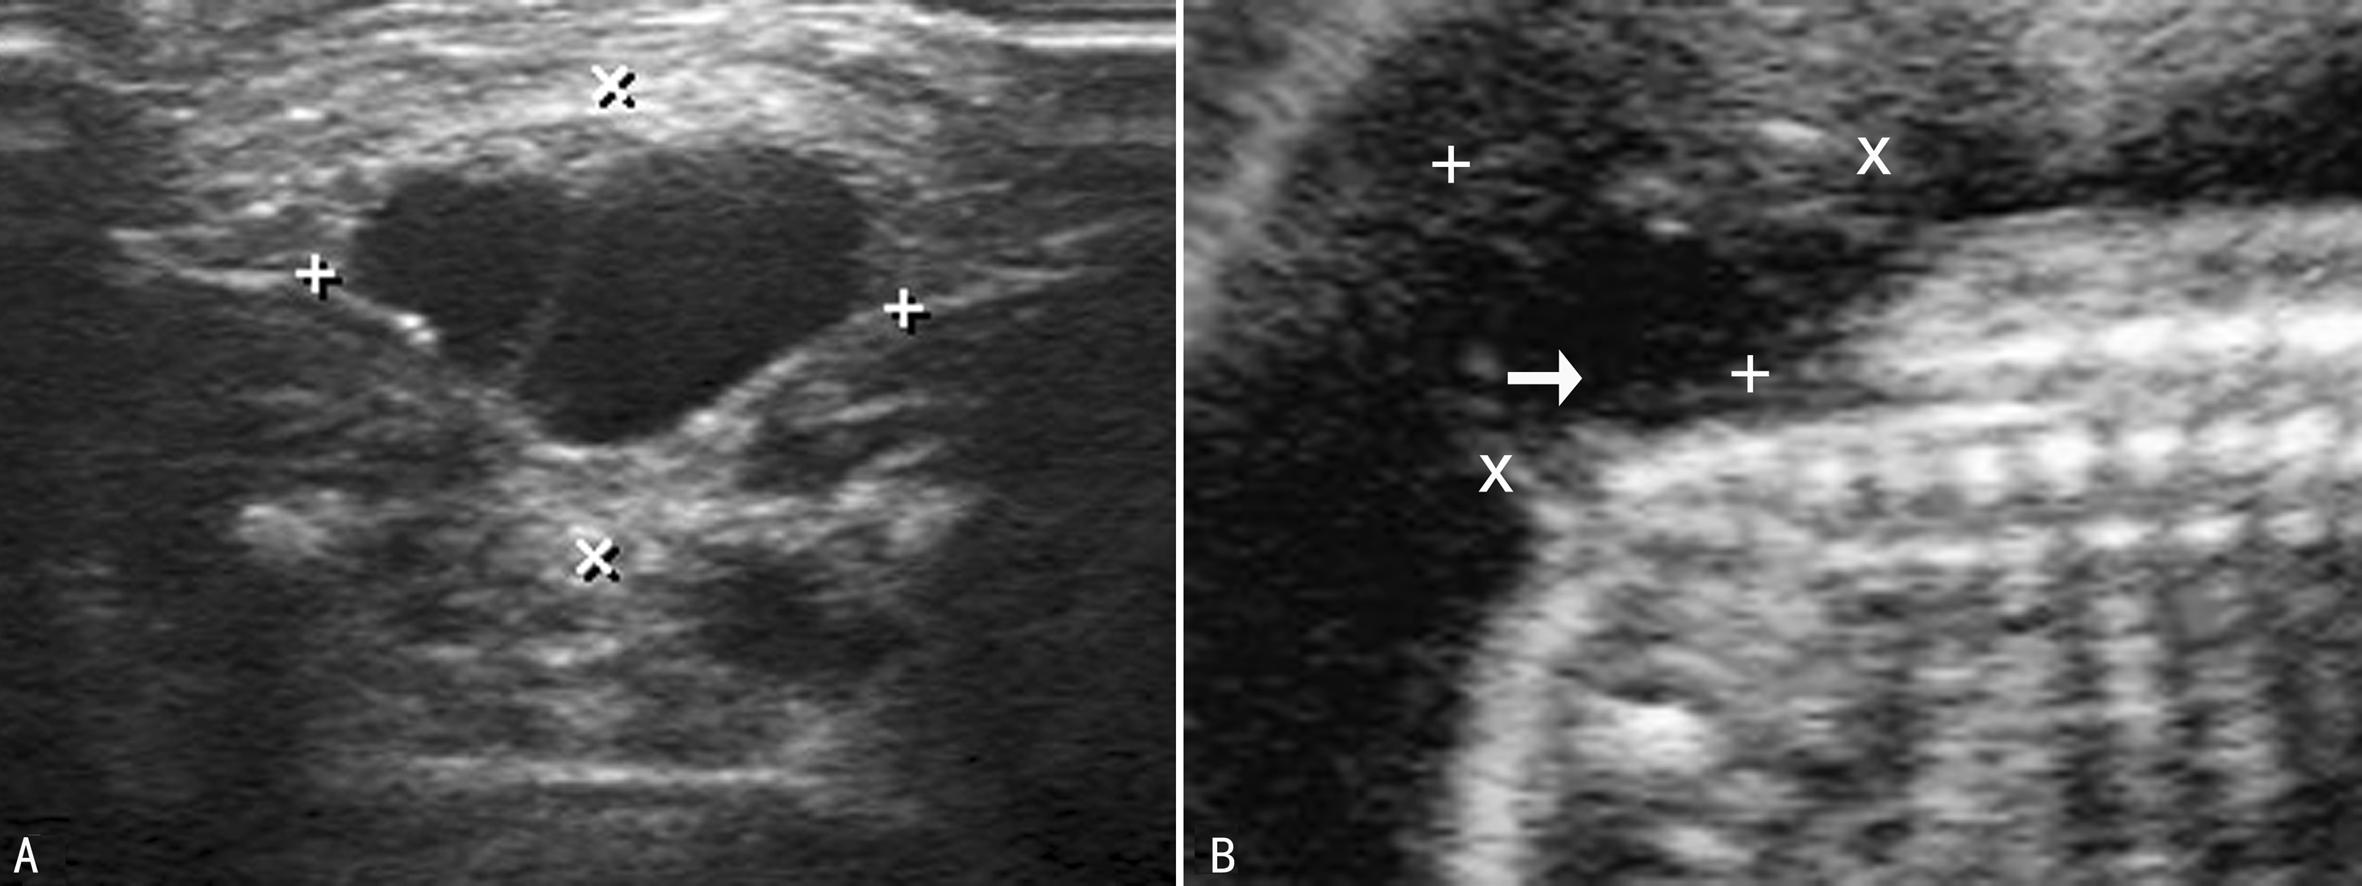

CSD类型不同,声像图表现各不相同。包块型CSD除局部皮肤完整外脊柱的声像图特征与OSD相同,横切面脊椎三角形骨化中心显示不清(图4、图1)或失去正常形态,位于后方的两个椎弓骨化中心向两侧分开,呈“U”形或者“V”形改变。脊柱冠状切面显示后方的两条平行的椎弓骨化中心在裂开处异常增宽,距离增大或部分消失。矢状面上突出的包块内可以看到由脑脊液形成的无回声,或由脊膜脊髓膨出的脑脊液内的不规则低回声组织(图5)。无包块型CSD的脊柱声像改变不明显,产前超声诊断困难。

图5 CSD脊膜脊髓膨出横断面(A)及矢状面(B)